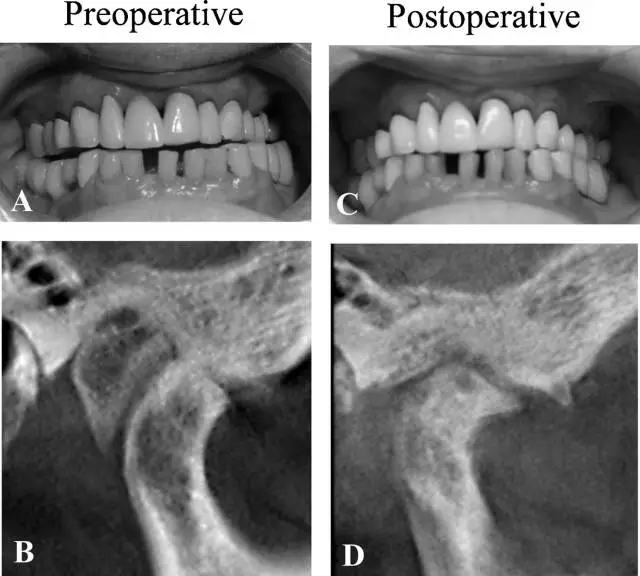

術前錐束 CT 見一自顳骨生長的外生骨疣幾乎填滿整個右側關節(jié)窩,約有 14 mm × 20 mm × 19 mm,髁突前下方扁平,骨皮質(zhì)不規(guī)則,呈骨關節(jié)炎影像。髁突后部見有骨沉積,關節(jié)間隙減小。

圖 2. 病例 2 的口內(nèi)照及 CT 圖像 (A,B) 術前 (C,D)術后

術后愈合良好,無明顯并發(fā)癥,病理檢查證實為骨軟骨瘤。術后 1 年影像學檢查發(fā)現(xiàn)髁突位置較術前更靠近關節(jié)窩中心,關節(jié)間隙增大,關節(jié)窩后部可能殘留有較小的骨軟骨瘤,術后 1 年及 3 年臨床檢查下頜中線對齊及恢復咬合,無關節(jié)區(qū)疼痛,開口度增加到 35mm。